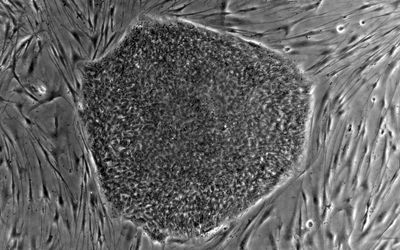

Kmenové buňky jsou tělu vlastní buňky, které se nacházejí v různých tkáních a orgánech. Nejčastěji jsou izolovány z kostní dřeně nebo z tukové tkáně. Kmenové buňky mají dvě základní funkce: schopnost sebeobnovy a schopnost obnovy a opravy poškozených tkání a buněk.